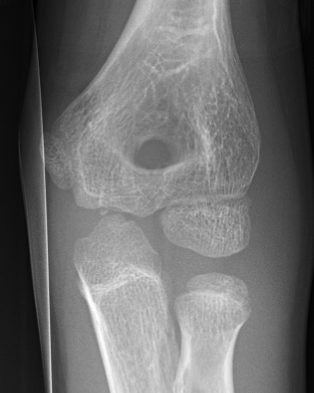

11 year old male: CRITOE